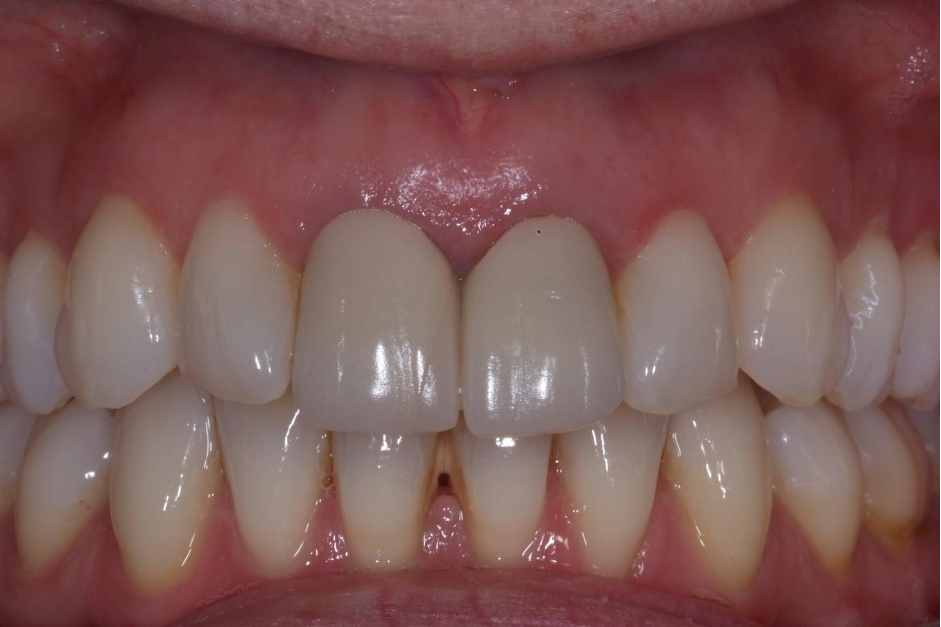

An example of one of the first cases that we did this way is below, including the most recent images of the case.

This illustrates the power of guided surgery and constant improvement.

Here is a more recent case…